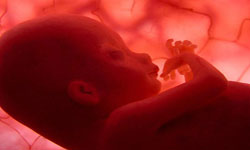

SEMANA 21 . TÚ... Tú útero empezará a subir por encima de tu ombligo, así que despídete de tu cintura. Y al estirarse la piel de tu tripa, puede picarte. Y TÚ BEBE... Mide unos 20cm.Su piel es sensible al tacto.

SEMANA 22 . TÚ... Notarás periodos de actividad y quietud en el patrón de movimientos de tu bebé. Y TÚ BEBE... Ya tiene párpados y cejas bienformados, pero los ojos todavía están fusionados. Aún tardará en abrirlos. Mide 21cm.

SEMANA 23 . TÚ... Has podido aumentar unos 2-3kg y te sientes pesada, sobre todo si tienes los pies hinchados. Y TÚ BEBE... Puede agarrar con sus manos, y el lanugo, el vello que le cubre, se oscurece.

SEMANA 24 . TÚ... Tu pechos pueden secretar calostro como preparación para la lactancia. Y TÚ BEBE... Aunque pesa menos de un 1kg, podría sobrevivir si naciera antes de tiempo. Está despierto entre 4 y 8 horas diarias. |